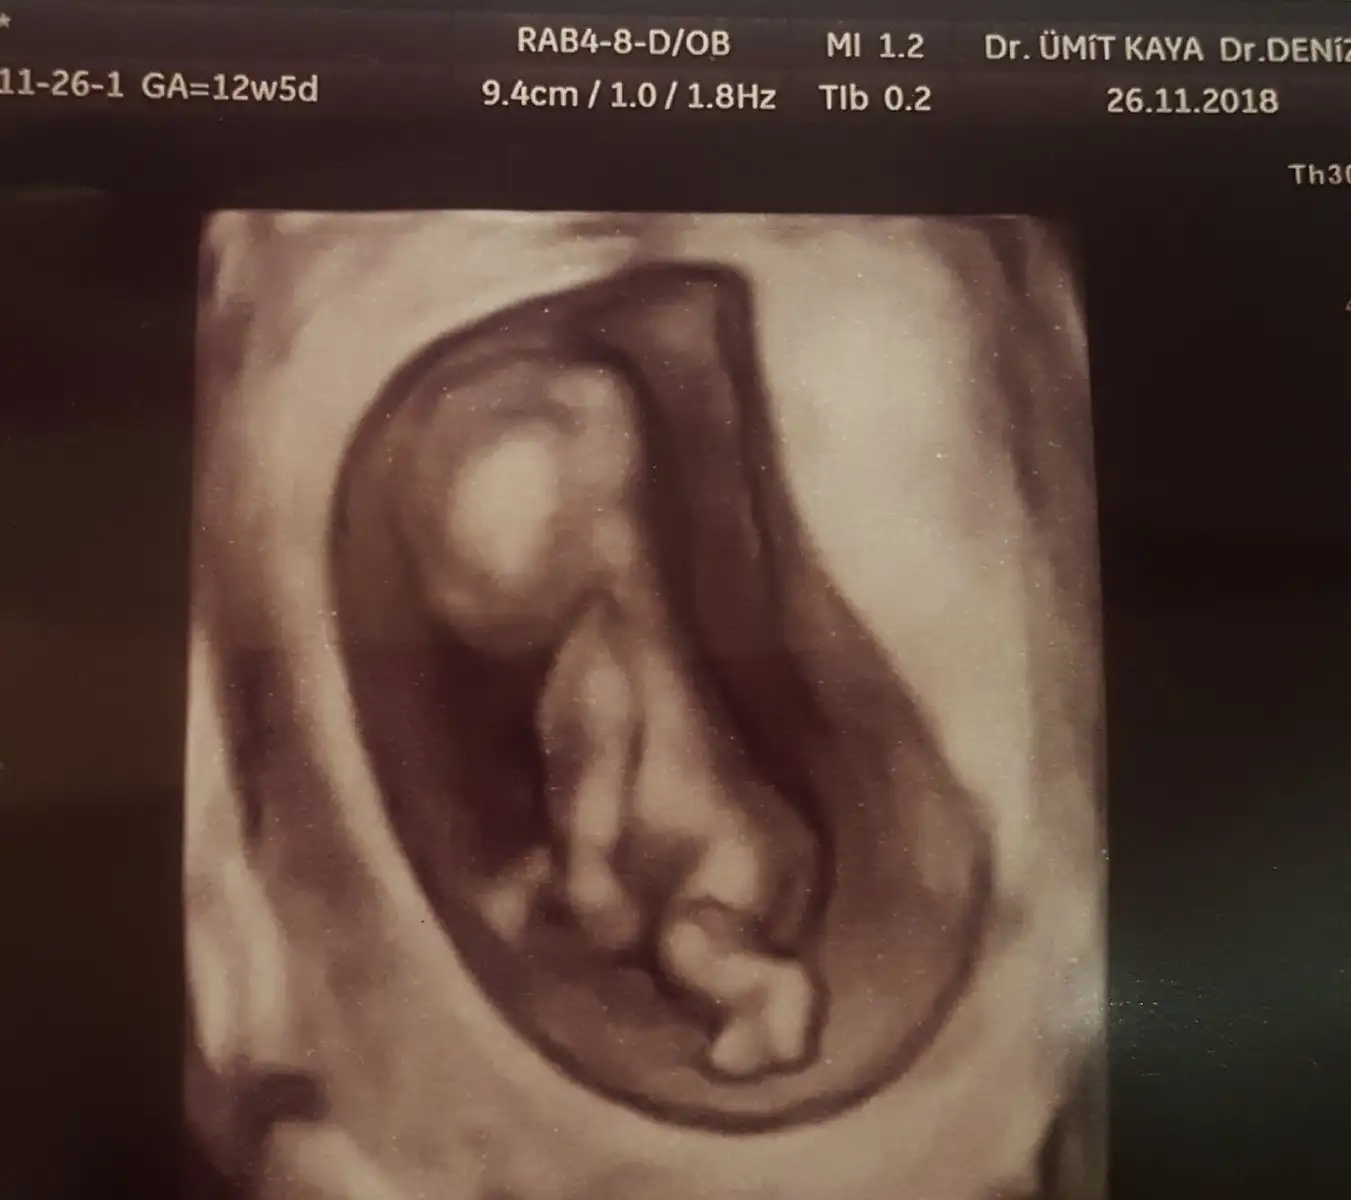

İlk doktor 11+4 te açı bulamamış kızı andırıyor demişti. Bugün başka doktora gittim 12+5 ti erkek dedi çıkıntı var ama erken daha dedi bilmiyorum yani farklı dediler

Bende çok ısrar ettim mecbur inceledi sağolsun :)) Ama daha çok küçük diye de ekledi. Bacak arasını gösterdi şuanda boş görünüyor ona göre söylüyorum bunu değişebilir dedi :)